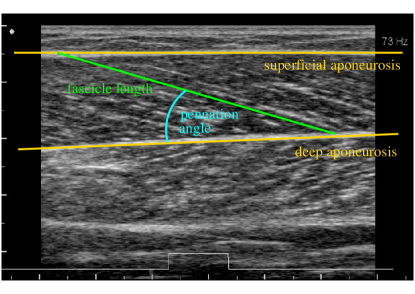

Human movement results from a coordinated activation of the skeletal muscles. The muscle fascicle length and their change in length is critical for the force and efficiency of the muscle. It is thus necessary to measure fascicle length, which is usually done from ultrasonic images [1, 2, 3]. An example of a B-mode ultrasound image of the muscle gastrocnemius medialis recorded with an ALOKA Prosound α𝛼\alpha7 can be seen in Fig. 1: the fascicles are spanned between the two aponeuroses.

As the fascicles are interrupted by noise and rarely are captured in their full length by the imaging process, their length must be computed from three different auxiliary observables: the position of the two aponeuroses and the fascicle orientation angle (pennation). Throughout the present paper, we make the simplifying assumption that both aponeuroses can be approximated by straight lines. The fascicle length can then be computed from the pennation angle at different positions on these lines. We thus only concentrate on the problem of finding the aponeuroses and estimating the pennation angle.

Refer to caption

Figure 1: Annotated example of an ultrasonic image of the muscle gastrocnemius medialis.